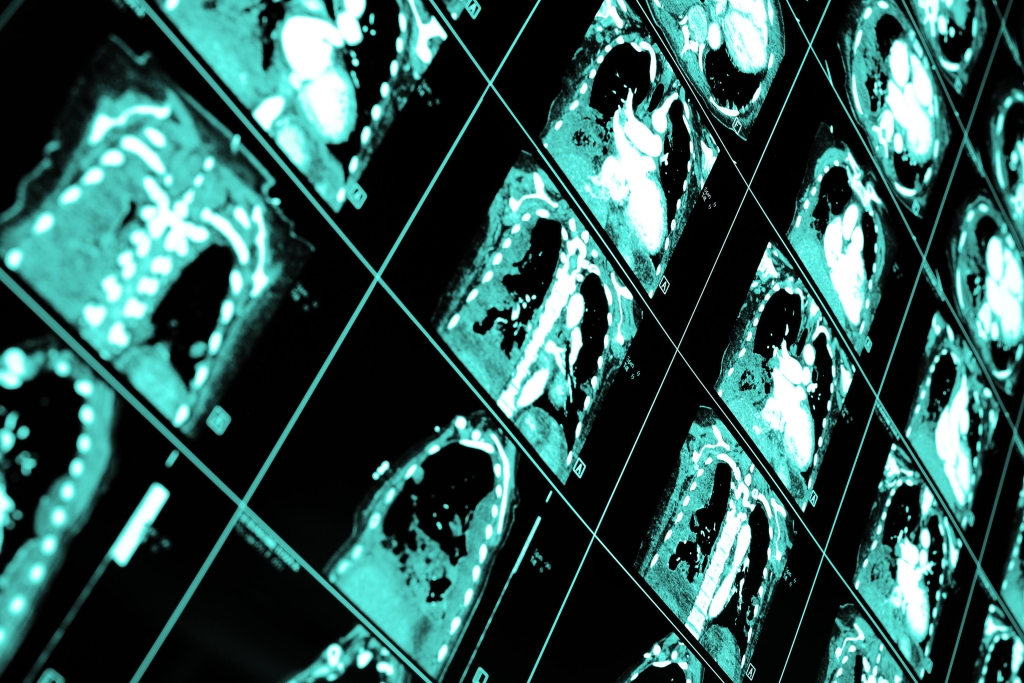

Al momento non ci sono programmi di screening per il tumore del polmone organizzati a livello nazionale, ma molti Paesi si stanno attrezzando. Negli USA gli esami con TC spirale vengono coperti dal sistema di rimborsi Medicare, in Cina ci sono sperimentazioni in varie province e diversi studi pilota nazionali sono stati avviati in Canada, Brasile, Australia, Corea, Giappone, oltre che in Polonia e nel Regno Unito. Ecco perché nel mese di febbraio 2020 le due principali società scientifiche di pneumologi e radiologi in Europa (European Respiratory Society e European Society of Radiology) hanno pubblicato un documento in cui riassumono evidenze e raccomandazioni per progettare in modo efficace e efficiente programmi di screening in Europa. Ricordano che quando si manifestano i sintomi del tumore al polmone (link) in nove casi su dieci è tardi e non sono più possibili trattamenti efficaci. Che una TC a basso dosaggio emette il 90% di radiazioni in meno rispetto a una TC del torace standard e ha il quadruplo delle chance di identificare un tumore molto piccolo. Concludono che è il momento di permettere ai cittadini europei di beneficiare di percorsi organizzati per la diagnosi precoce del tumore al polmone.

Più di recente, un gruppo di lavoro internazionale ha pubblicato sulla rivista Cancers una serie di raccomandazioni, che includono aspetti chiave, come la necessità di modelli di prevenzione del rischio per selezionare le persone che più beneficeranno dei controlli (anche con la ricerca di marcatori molecolari nel sangue), di una rete di centri di riferimento per il controllo di qualità. Si raccomanda di unire al controllo con la TC anche un programma di sostegno e educazione per incentivare lo stop al fumo e per sostenere chi vuole smettere o ha smesso. E di gestire attentamente le patologie concomitanti che la TC del torace può identificare aldilà del cancro, soprattutto la bronchite cronica ostruttiva (BPCO) e le calcificazioni delle coronarie.